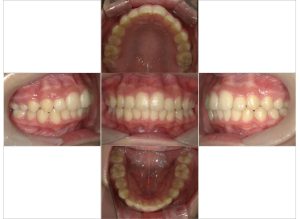

今回は上下の歯列の拡大とそれによって生じたスペースを利用して重なりのある前歯の重なりを取り除いています。

矯正にかかった期間は2年間、歯の移動の中で上下の12歳臼歯の萌出も起こったのでコントロールを行いながらの治療となります。

治療後の歯並びを維持するためにもリテーナーの使用と併せてお口周りの筋肉の維持も重要になってきます。